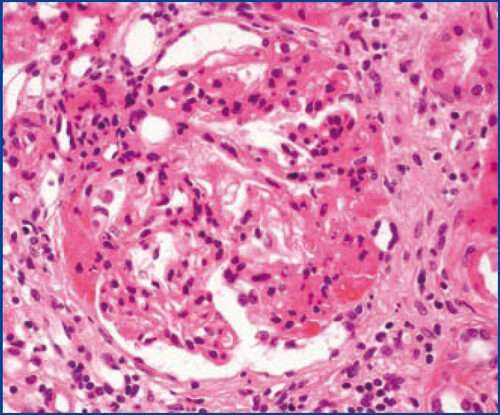

El diagnóstico de la glomeruloesclerosis segmentaria focal requiere, de manera casi universal, una biopsia renal, ya que los hallazgos clínicos y de laboratorio por sí solos no son suficientes para confirmar la enfermedad. La biopsia permite obtener una muestra de tejido renal que puede ser evaluada bajo el microscopio, lo que proporciona información crucial sobre el patrón de daño y las características morfológicas de los glomérulos. En la glomeruloesclerosis segmentaria focal, el análisis mediante microscopía óptica revela la esclerosis segmentaria de algunos glomérulos, es decir, la cicatrización localizada en segmentos de los glomérulos, pero no en todos los glomérulos de la muestra, lo que es característico de esta enfermedad.

Cuando se realiza una inmunofluorescencia sobre el tejido renal, se observa la presencia de inmunoglobulina M y complemento C3 en las lesiones escleróticas. Sin embargo, se asume que estos componentes inmunitarios están simplemente atrapados en los glomérulos escleróticos debido a la alteración de la barrera de filtración, y no se consideran directamente patogénicos en el desarrollo de la enfermedad. Es decir, aunque estos componentes son detectados en los glomérulos dañados, no juegan un papel activo en la causación del daño renal, sino que reflejan una respuesta secundaria a la alteración estructural de los glomérulos.

En cuanto a la microscopía electrónica, los hallazgos en la glomeruloesclerosis segmentaria focal son similares a los observados en la enfermedad de cambio mínimo, otra patología glomerular. La característica principal es el borramiento de los procesos de los podocitos, que se refiere a la pérdida de la estructura normal de estas células especializadas, responsables de mantener la barrera de filtración glomerular. El borramiento de los procesos de los podocitos es una manifestación clave de la disfunción de estos y contribuye a la pérdida de proteínas en la orina, característica del síndrome nefrótico.